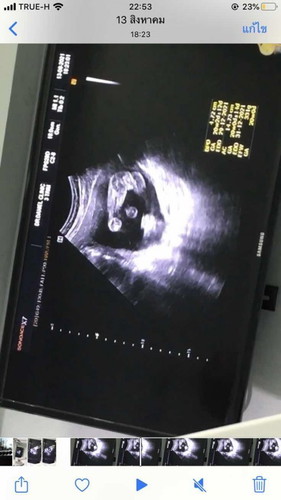

น่าจะผู้หญิงนะคะเท่าที่ดูจากกลีบถ้าเปนผู้ชายน่าจะมีจู๋โผล่ออกมาแล้วค่ะ

ลูกสาว นะคะ จากภาพรือ หว่างขาน้องค่ะ

ผญ.ค่ะแม่ ของเราผู้ชายจู๋โด่เลยจ้า

น่าจะผู้หญิงค่ะ

น่าจะผญ.นะคะ

ลูกสาวค่าาา